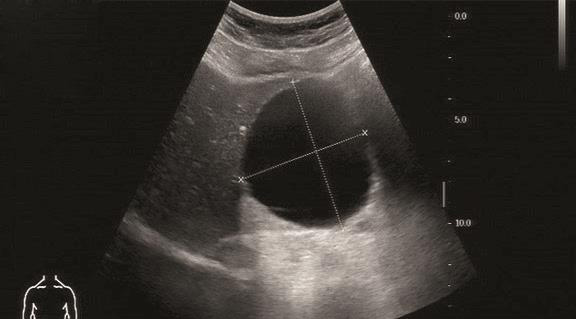

(1)典型肝囊肿,呈边界清晰的圆形或椭圆形,囊壁薄而清晰,内部均匀无回声,后方回声增强,可伴侧方声影,囊壁无彩色血流信号(图1-9-1、图1-9-2)。

图1-9-1 肝内多发囊肿灰阶超声图像